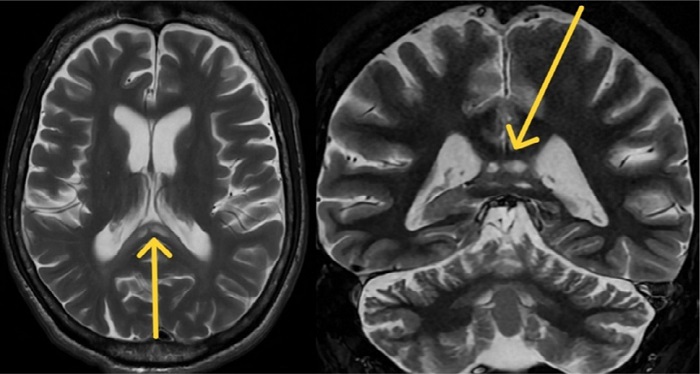

Brain magnetic resonance imaging (MRI) reveals global atrophy, predominantly affecting the cerebellar vermis, with three lesions exhibiting hypointensity on T1 and hyperintensity on T2 in the splenium of the corpus callosum ( Figures 1 and 2). No restriction in water diffusion or enhance with gadolinium was noted.

The typical presentation involves lesions with a cystic appearance or an edema/demyelinating substrate, generally located in the corpus callosum, which may also affect the deep white matter. The number and characteristics of the lesions may change with disease progression. Fewer lesions, restricted diffusion, and gadolinium enhancement typically indicate an acute process 2, 4, 5.